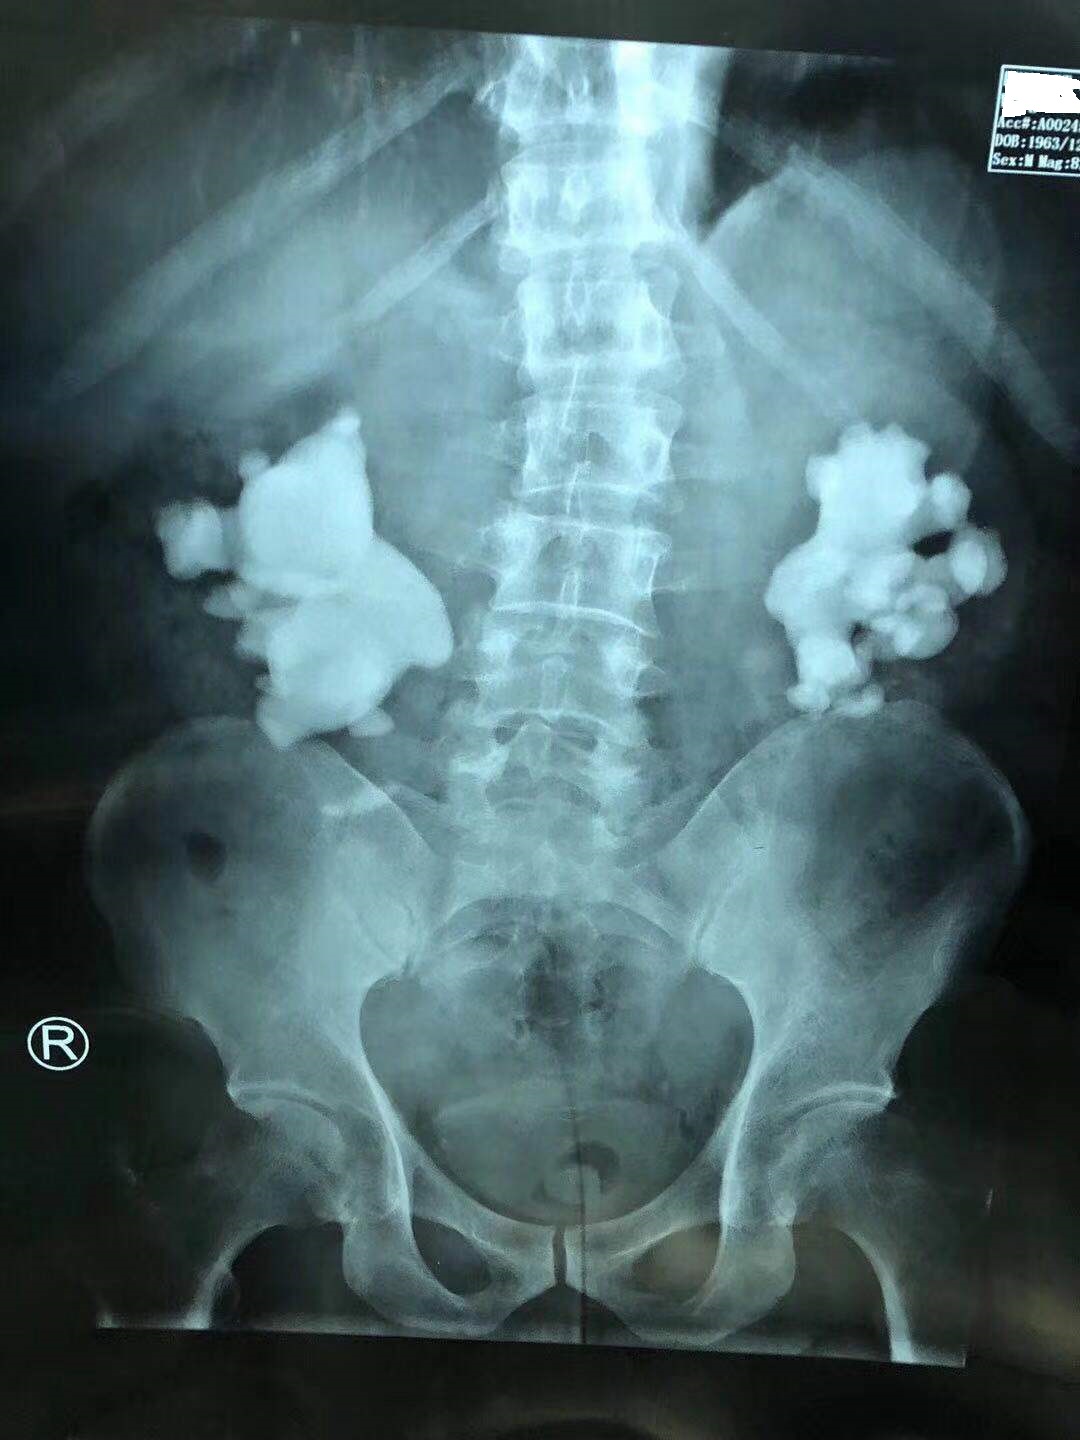

林先生的双肾鹿角形结石

为了挽救他的肾脏,经过深思熟虑后,我们制定了"分期多通道PCNL"手术方案,首先开放两个"经皮肾通道"处理干净右肾鹿角形结石。

第一次手术取净右肾结石!